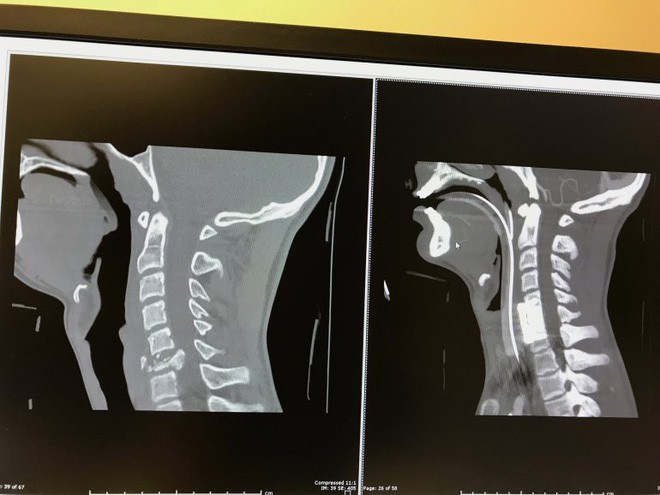

Trực thăng lập tức có mặt và Alex đã được đưa đến bệnh viện nhi Riley ở Indianapolis. Tại đây, các bác sĩ sau một thời gian kiểm tra kỹ lưỡng đã thông báo hung tin đến gia đình Alex: cậu bé bị chấn thương ở đốt sống C6. Bác sĩ Jeffrey Raskin - bác sĩ giải phẫu thần kinh nhi khoa của bệnh viện - cho biết rằng tình trạng liệt của Alex sẽ trở nên nghiêm trọng nếu trong vòng 72 giờ tới, cậu bé không có bất kì tiến triển nào. Khi đó, chỉ có 10% cơ hội Alex có thể đi lại được mà thôi.

Ảnh chụp chấn thương của Alex. (Ảnh: fox59)

Vậy là cậu bé phải trải qua cuộc phẫu thuật dài 4 giờ đồng hồ, sau đó được chuyển đến phòng chăm sóc tích cực 1 tuần. Alex không thể cử động bất kì bộ phận cơ thể nào từ cổ trở xuống và tình trạng của cậu bé khi đó rất tệ.